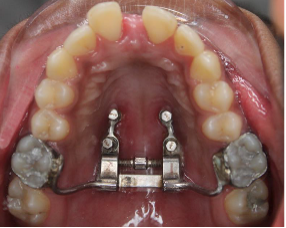

Fig.1 Bone-bone anchored designThe support arms can be temporarily bonded with composite to stabilize the expander for TAD insertion and cut off afterwards

Fig.2 Bone-bone anchored designThe support arms can be temporarily bonded with composite to stabilize the expander for TAD insertion and cut off afterwards